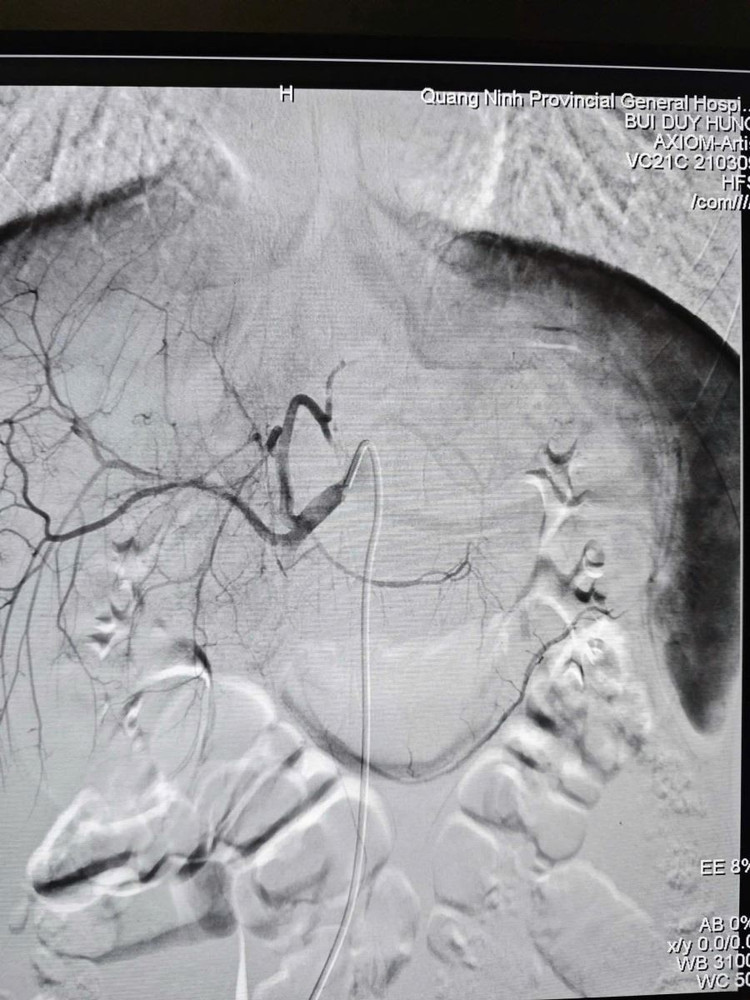

Hình ảnh sau nút mạch điều trị chấn thương gan, ổ chảy máu đã được nút tắc./Ảnh BV

Sau 60 phút, ca can thiệp thành công tốt đẹp, hình ảnh chụp kiểm tra cho thấy điểm chảy máu đã được cầm hoàn toàn. Huyết động bệnh nhân ổn định và được chuyển hậu phẫu theo dõi với tiên lượng phục hồi. Thành công của ca bệnh khẳng định hiệu quả của mô hình hoạt động đồng bộ, năng lực chẩn đoán tại chỗ nhanh, chính xác ngay từ đầu nhờ CT Scanner và nhân lực chất lượng làm chủ kỹ thuật nút mạch giúp xử trí chấn thương nhẹ nhàng, hiệu quả cao.